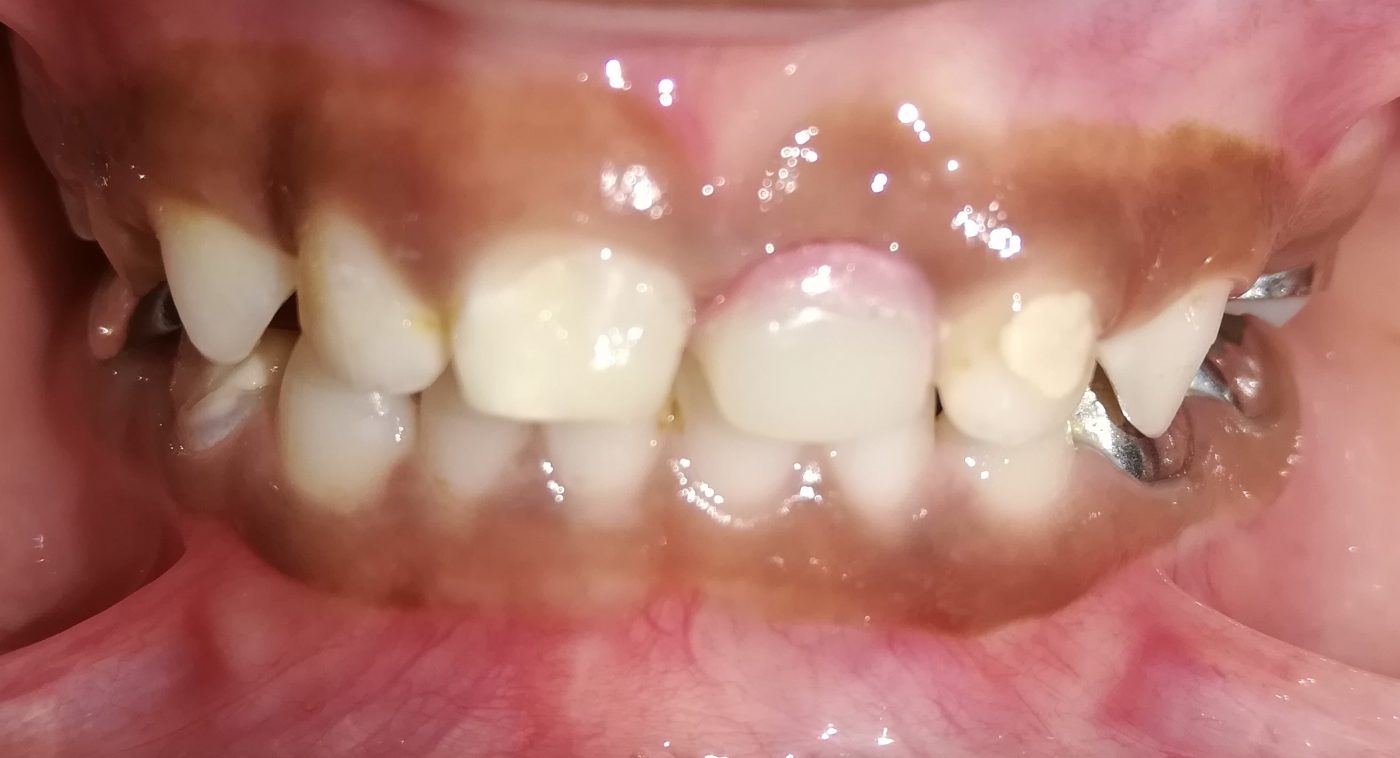

We at the Department of Pediatric & Preventive Dentistry focus on comprehensive oral health care needs of a child from infancy to adulthood and provide comprehensive, therapeutic as well as preventive care to all children including those with special care needs.

Treatment and Services